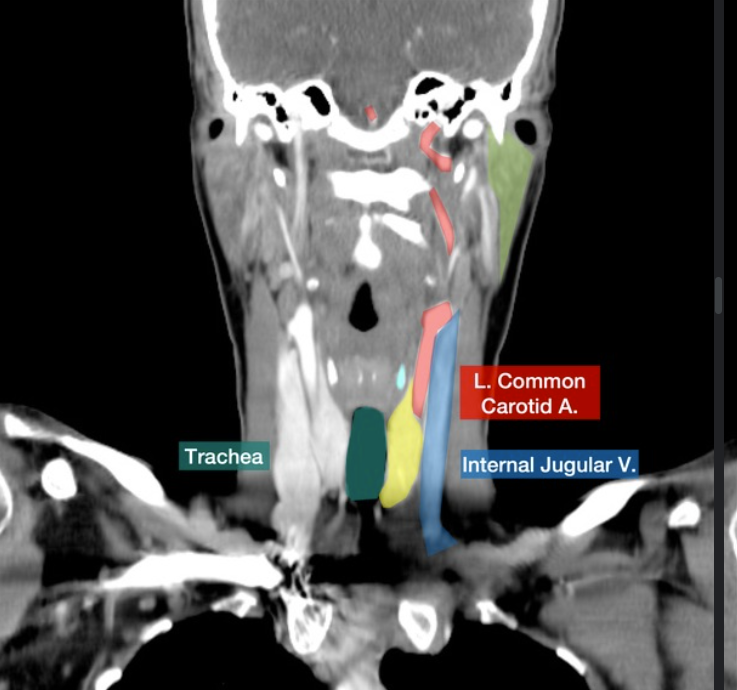

Please label this coronal CT scan